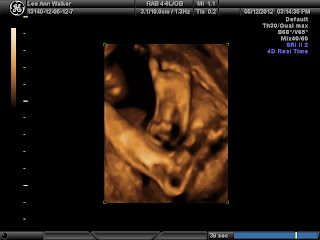

so news. Ryleigh does have Dandy Walker but only the

Variant form not syndrome, if she didn't have the heart condition it would have